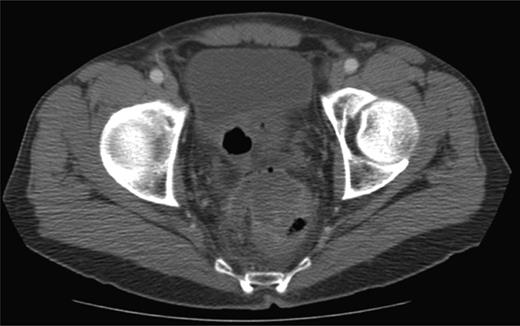

Contrast-enhanced computed tomography (CT) scan revealed the presence of diverticulosis and perirectal mesenteric stranding concerning for diverticulitis (Fig. 1); therefore, the patient was admitted and treated empirically for the same with i.v. antibiotics. He was discharged several days later with a 2-week course of amoxicillin clavulanate.

CT scan depicting perirectal stranding without definite abscess formation.